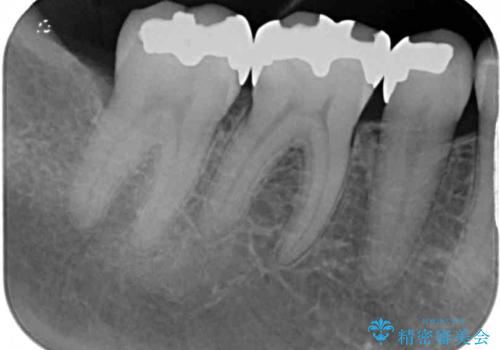

- 銀歯をセラミックにしたいとのことで来院された患者様です。

まず麻酔をして銀歯を外し、むし歯を除去し、形を整えて型取りします。

インレーを装着するときは、唾液や血液による接着力の低下を避けるためにラバーダム防湿を行いました。